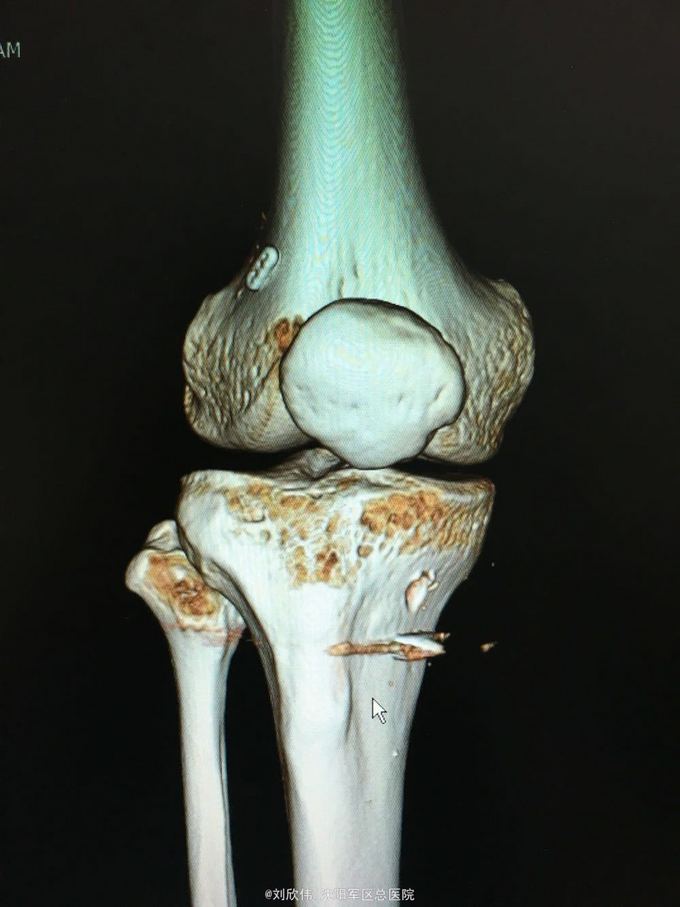

训练致右膝肿痛伴活动受限3个月 自觉脱臼感

右膝lachman试验,轴移试验阳性 MRI提示ACL已显示不清,半月板后角高信号(但术中未见撕裂,mri存在假阳性)

右膝前交叉韧带断裂 右膝半月板损伤 手术方法如题,直接上图